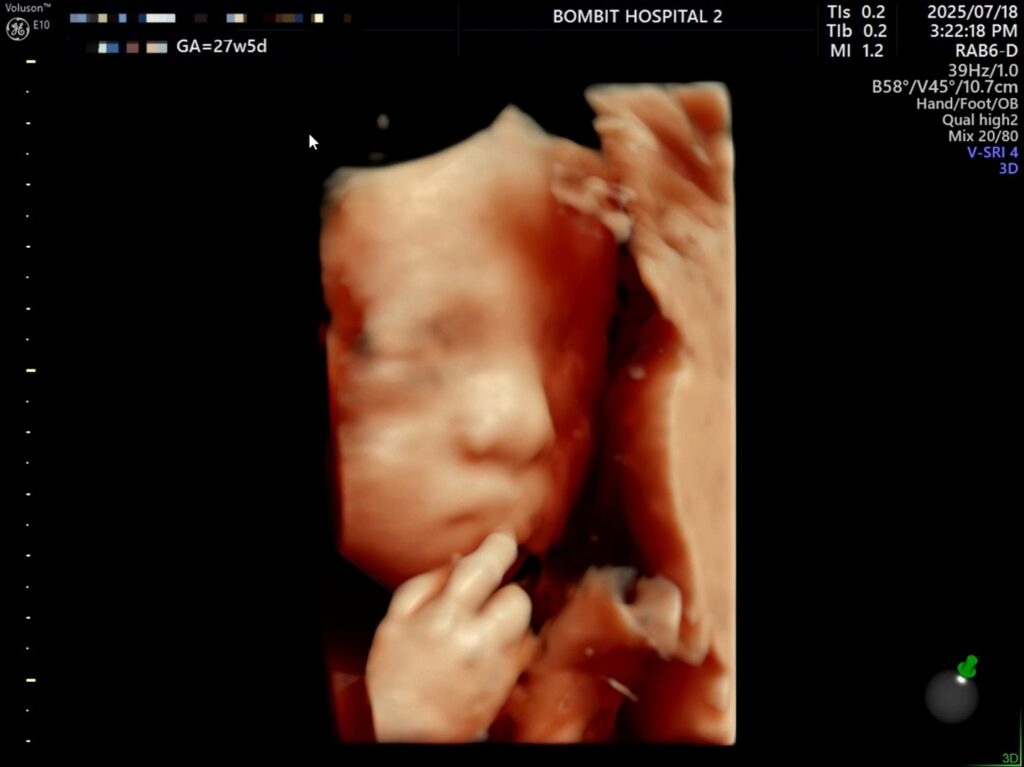

7월 18일, 27주 5일.

어제 단비의 입체초음파를 보았다.

체중은 상위 84%, BPD(머리 폭)이 상위 97%다. FL(대퇴골 길이)도 상위 91%..

입초로 본 단비 얼굴은 정말 너무너무 귀여웠다!! 보면서 코가 복코같이 눌려있다고 생각했는데,, 선생님은 아기 콧대가 높다고 했다. 엄마를 닮아서 그런 듯(?)ㅋㅋㅋ